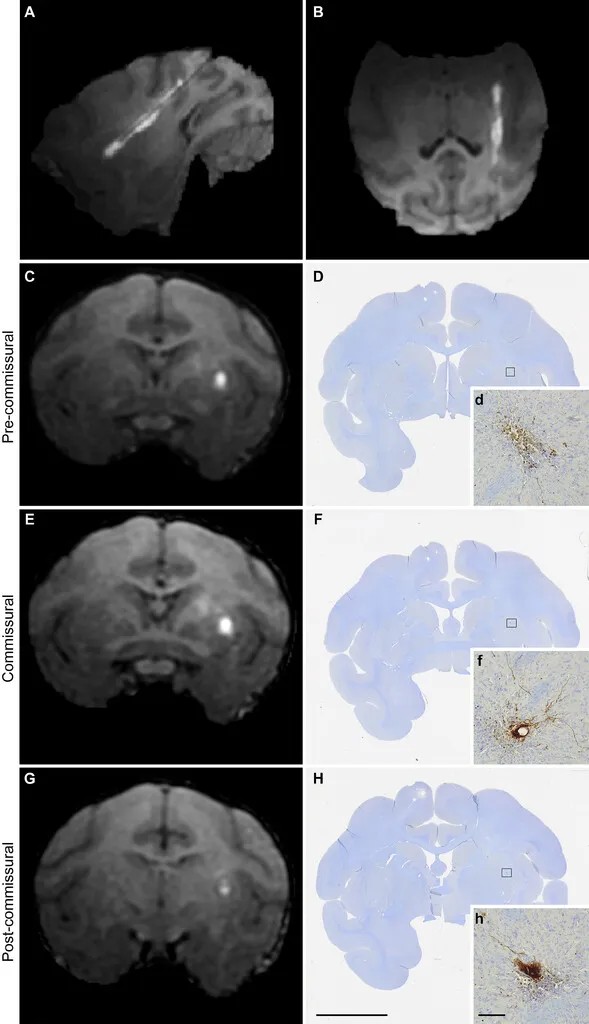

利用术中核磁共振成像技术引导细胞移植到大脑特定区域的过程,以及移植细胞在术后30天的存活和分布情况。(D),(F)和(H):在细胞移植后30天,在与(C),(E)和(G)相对应的三个冠状面水平上检测到STEM121阳性的人类细胞,表明移植的细胞存活并分布在注射区域。(d),(f)和(h):(D),(F)和(H)中方框区域的更高放大倍数图像,更清晰地展示了STEM121阳性细胞的分布。